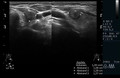

• Ultraschall der Schilddrüse inklusive Perfusion und Elastografie